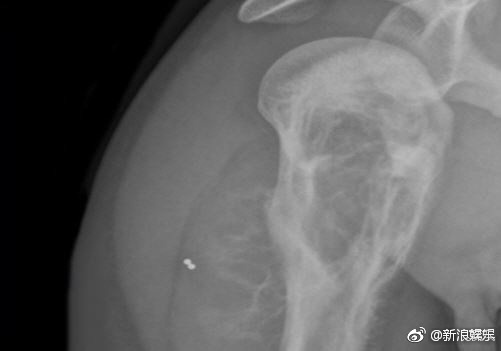

Hơn nữa, Yoo Ah In từng bị thương phần cơ vai bên phải trong khi quay bộ phim Tough as Iron năm 2013. Tình trạng của anh trở nên trầm trọng hơn khi thực hiện tác phẩm Veteran năm 2014.

Đạo diễn của Veteran cho hay: “Cảnh quay cuối là cảnh mà Yoo Ah In phải tham gia vào cuộc chiến tay đôi với Hwang Jung Min. Tôi rất biết ơn Yoo Ah In bởi dù đôi tay bị run do chấn thương ở vai nhưng anh đã thể hiện tinh thần chiến đấu cho đến tận cùng và kết thúc việc quay phim mà không cần đóng thế”.